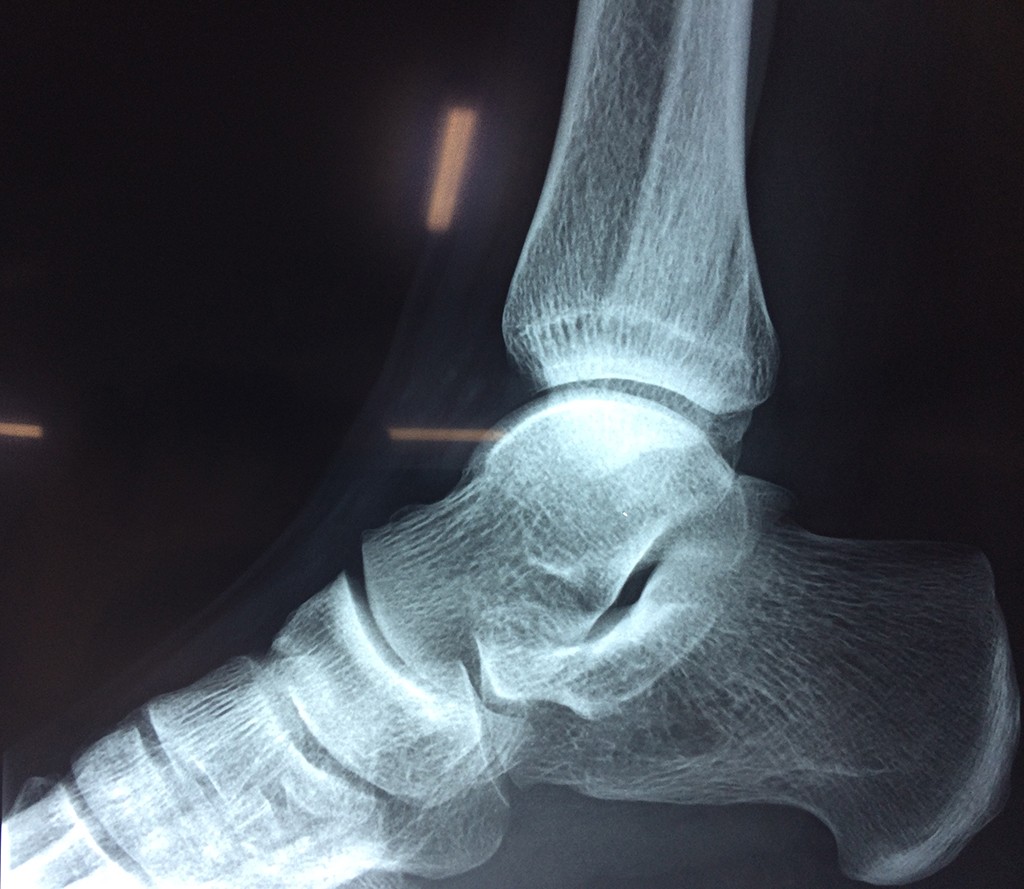

Una fractura de tobillo es la rotura de uno o más de los huesos del tobillo. Estas fracturas pueden ser: